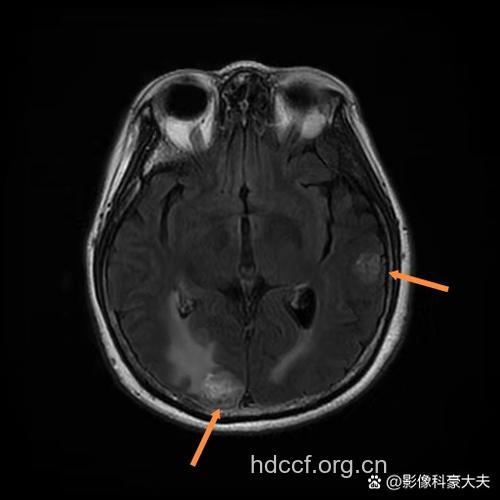

研究结果显示:HIV组出现了量化的总体(p=0.0547)和皮质(p=0.0109)中灰质的减少。用分离图像分析公式对各脑区进行分析后发现持续存在脑皮质减少(p=0.042)和第三脑室扩大(p=0.046)。早期HIV感染组在不少神经精神测试方面的表现也较差,最大的差异在精神运动速度(p=0.001)。

该研究显示:HIV感染早期即出现结构改变。这个结果挑战了HIV感染早期脑部无受损的假说。脑对病毒-宿主最初相互作用过程中存在易感性,早期HIV感染就存在神经损伤,应进一步研究新的神经保护策略